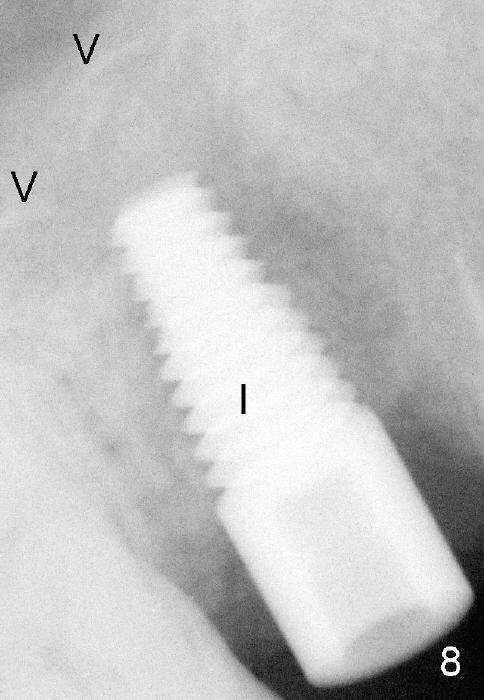

Four months after implant removal, the bony defect appears to increase (Fig.5). Reamers (Fig.6 R)and osteotome (Fig.7 O) are short of the sinus floor (arrowheads). A 5x14 mm tapered implant is placed with primary stability (Fig.8 I). The implant is placed ~ 2 mm deeper (Fig.9). No bone graft is used for sinus lift. There is no complication. The sinus floor appears to be repaired 4.5 months postop (Fig.10). Fig.11 (trimmed from panoramic X-ray) is taken 1 year 7 months post cementation. The bone remains stable 4 years 2 months post cementation (Fig.12); the mesial defect is most likely related to extraction trauma (*).